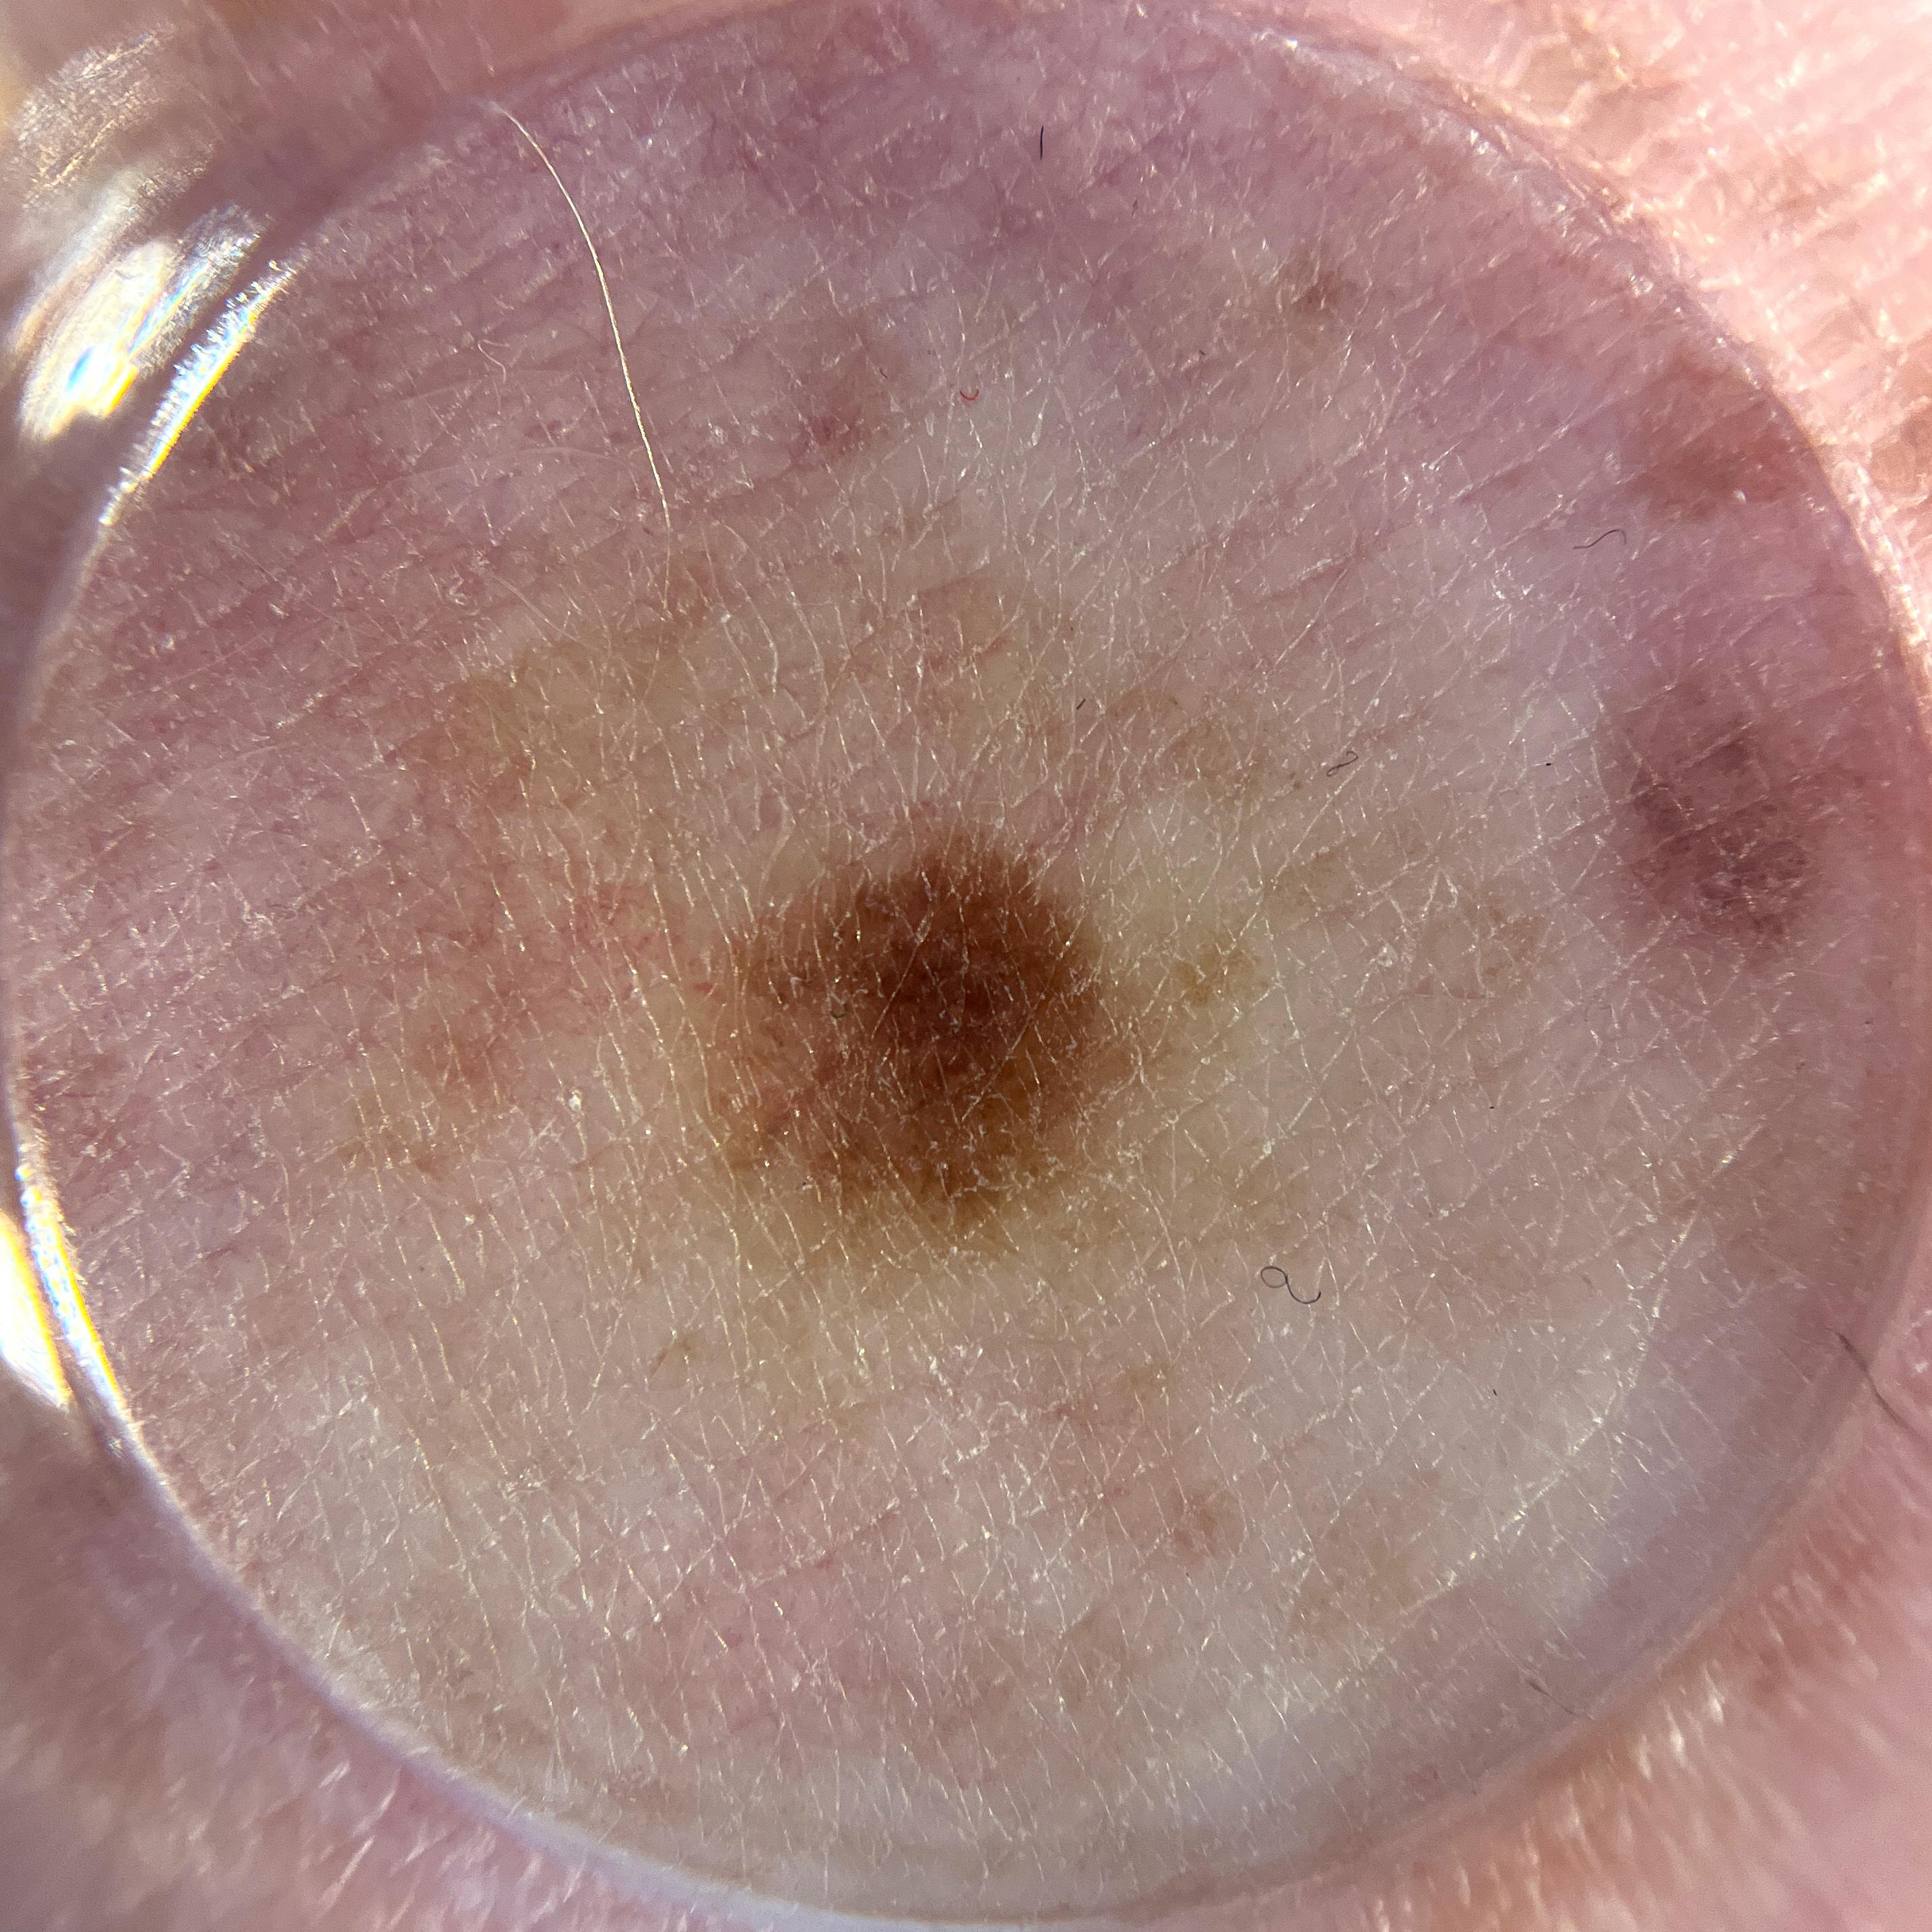

ISIC_0472493

2868 x 2868

Clinical

Field Value

acquisition_day 282

age_approx 50

anatom_site_1 Trunk

anatom_site_2 Posterior trunk

anatom_site_general posterior torso

concomitant_biopsy False

diagnosis_1 Benign

diagnosis_confirm_type single image expert consensus

family_hx_mm True

image_manipulation instrument only

image_type dermoscopic

lesion_id IL_1566797

patient_id IP_0266928

personal_hx_mm True

sex female